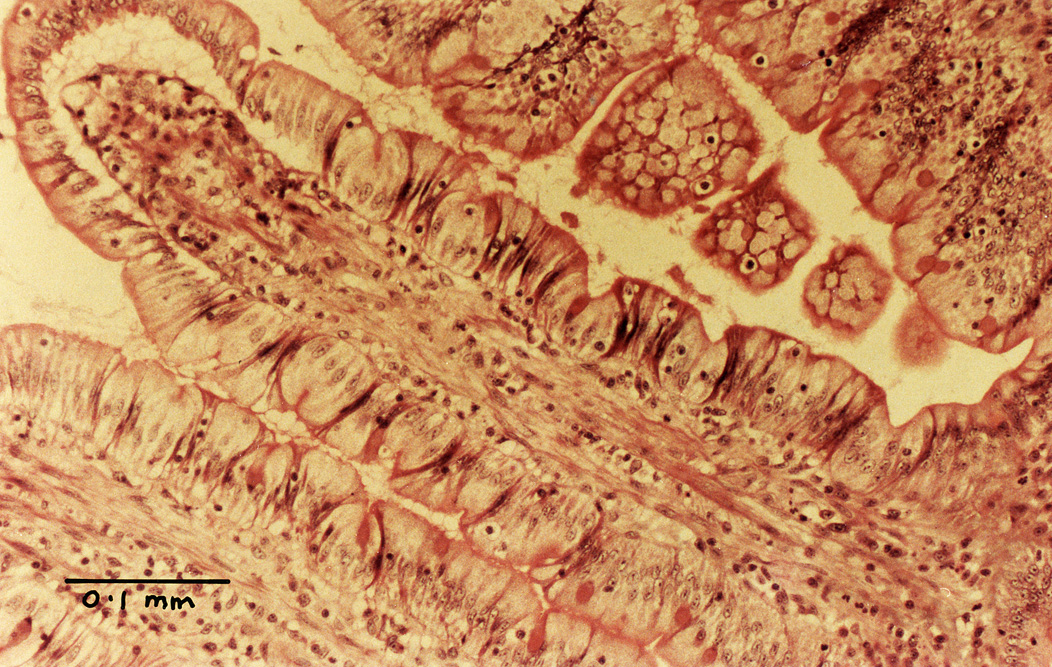

The lining of the small intestine has a very large surface area to facilitate absorption of digested food. The lining has circular folds, and on the surface of the folds there are finger-like villi. The cells covering the villi also have microvilli on their outer surface - these are best seen with the electron microscope. These adaptations increase the surface area.

low-power view of

several villi in section

medium-power view

of villus